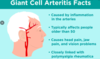

What is giant cell arteritis and what is the typical aetiology?

- Chronic vasculitis of large and medium vessels in the scalp, neck and arms.

- Occurs in people over 50 and associated with polymyalgia rheumatica

- Usually inflammation of arteries originating from arch of aorta

What are some risk factors for GCA?

- >50 years old (1 in 500)

- Caucasian

- Female

- Polymyalgia rheumatica

- Genetic Predisposition with HLA-DR4

What are the symptoms of GCA?

- Headache

- Scalp tenderness especially over temporal artery

- Jaw/tongue claudication on mastication

- Amaurosis fugax

- Blindness, diplopia, blurring

- Constitutional symptoms e.g malaise, weight loss

When is GCA an emergency?

- Any visual symptoms as there is a risk of irreversible bilateral vision loss

- Visual symptoms can present weeks-months after onset of other symptoms

What tests should you order if you suspect GCA?

- ESR/CRP: raised

- Platelets: raised

- Hb: lower

- Temporal artery biopsy: do not wait for this to start steroids, also may be negative biopsy due to skip lesions

How is GCA treated?

If acute visual symptoms

- Immediate IV methylprednisolone for 1-3 days

If just GCA

- Prednisolone PO 60-100mg for at least 2 weeks then consider tapering

- Low dose aspirin to reduce thrombotic risk

- PPI, Adcal and Bisphosphonate if long term steroids